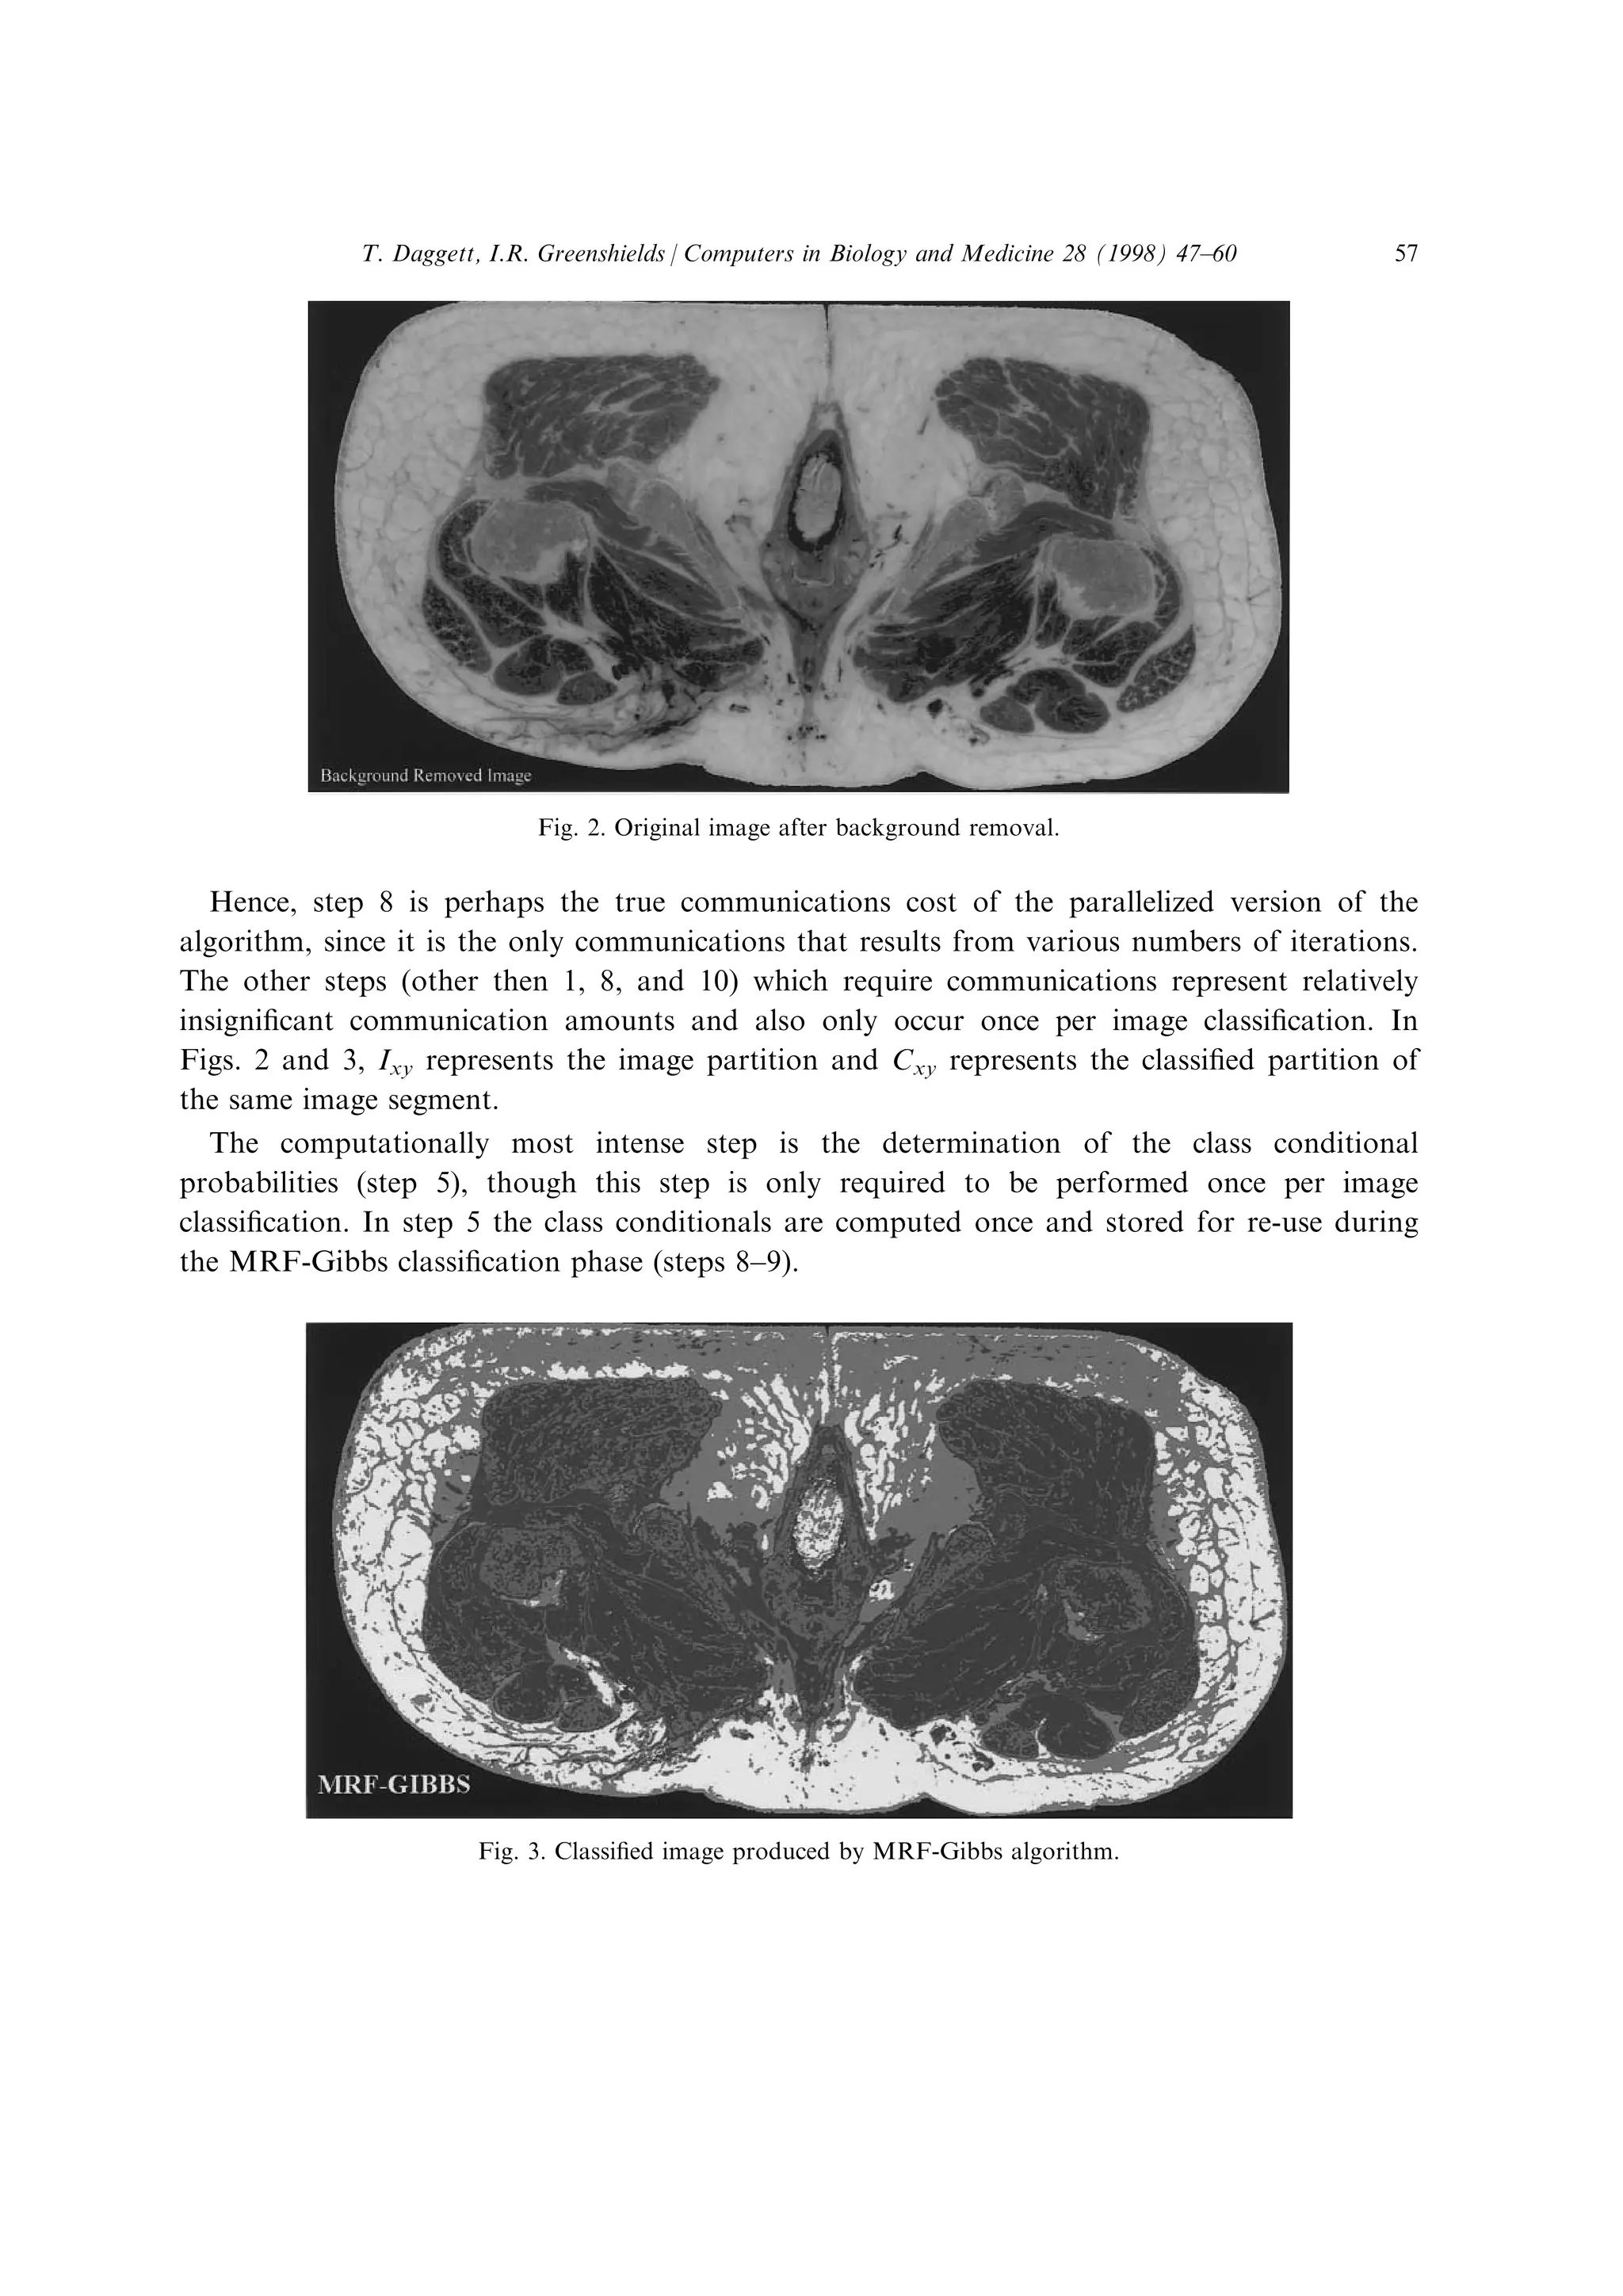

Hence, step 8 is perhaps the true communications cost of the parallelized version of the

algorithm, since it is the only communications that results from various numbers of iterations.

The other steps (other then 1, 8, and 10) which require communications represent relatively

insigni®cant communication amounts and also only occur once per image classi®cation. In

Figs. 2 and 3, Ixy represents the image partition and Cxy represents the classi®ed partition of

the same image segment.

The computationally most intense step is the determination of the class conditional

probabilities (step 5), though this step is only required to be performed once per image

classi®cation. In step 5 the class conditionals are computed once and stored for re-use during

the MRF-Gibbs classi®cation phase (steps 8±9).

Fig. 2. Original image after background removal.

Fig. 3. Classi®ed image produced by MRF-Gibbs algorithm.